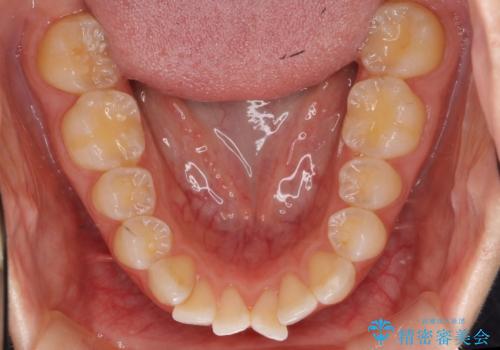

前歯のガタガタ 歯を削らずに自然な美しさを手に入れました

- 前歯のガタガタを主訴に来院。

結婚式を控えていたため、まずは前歯を並べて挙式を迎えました。

結婚式の日は前歯の部分の装置を外しています。

挙式後、矯正治療の続きを行いました。

がたがたが著しかったため、上下左右の小臼歯を抜歯しています。

矯正治療のメリットは天然歯を並べるため、被せ物で無理に治す治療と比較して矯正後に人工物の心配をしなくて良いところです。